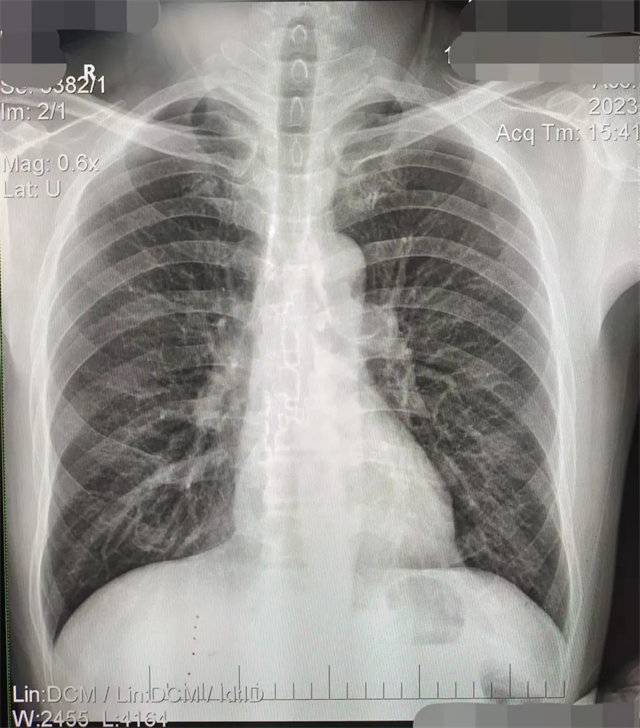

拍攝的不合格胸片的缺陷和解決方法

缺陷:左肩胛骨部分與左肺野重疊。

解決:使患者左肩旋前緊貼成像件重新曝光。